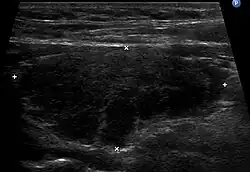

Ultrasound imaging of the thyroid gland (right lobe longitudinal) in a person with Hashimoto thyroiditis

Ultrasound

Ultrasound imaging of the thyroid showing Hashimoto's thyroiditis

An ultrasound may be useful in detecting Hashimoto thyroiditis, especially in those with seronegative thyroiditis,[13] or when patients have normal laboratory values but symptoms of autoimmune thyroiditis.[47] Key features detected in the ultrasound of a person with Hashimoto's thyroiditis include "echogenicity, heterogeneity, hypervascularity, and presence of small cysts."[13] Images obtained with ultrasound can evaluate the size of the thyroid, reveal the presence of nodules, or provide clues to the diagnosis of other thyroid conditions.[47]